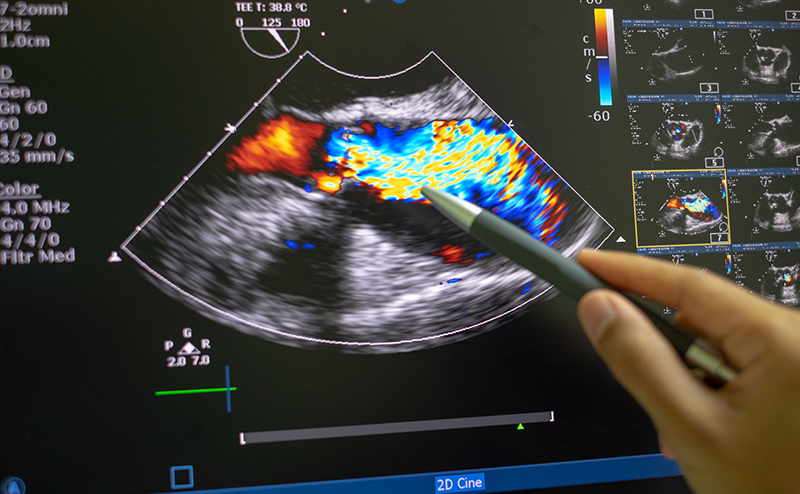

The point-of-care echo shown above surprised the treating physicians. Notable findings include severe RV dilation, RA enlargement, and a trace effusion. What are some tools to distinguish RV dilation in the setting of acute pulmonary embolism (PE) versus chronic RV dilatation such as in pulmonary hypertension (PAH)? Right ventricular dilation can occur in both, as well as evidence of strain or reduced RV systolic function. Distinguishing the two is a critical point in the diagnostic pathway and subsequent treatment regimen for these disease states. The brief synopsis below will outline the quantitative echocardiographic approach to this problem.